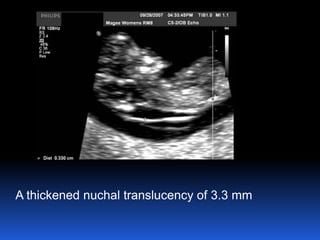

A thickened nuchal translucency of 3.3 mm

1. Screening for Down's syndrome

CRL measures from 45 mm to 84 mm (11-14 W)

Use the combined screening test:

 Nuchal translucency

 ßHCG,

 Pregnancy-associated plasma protein-A

(PAPPA)

calculate the risk of Down's syndrome